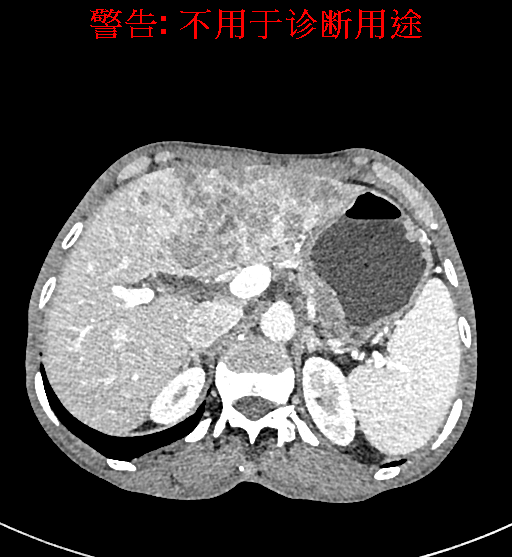

实验室检查: 血常规:WBC 4.89*109/L,RBC 3.64*1012/L, HB 119.00g/L, HCT 35.40%,PLT 123*109/L,RET% 0.48%, RET 0.017*1012/L, IRF 2.00%生化全套:ALT 56.00U/L AST 60.00U/L, LDH 312.00U/L TP 72.08g/L ALB 32.44g/L, GGT 101.00U/L,TBA 21.90umol/L,A/G 0.82,ADA 23.00U/L, PAB 94.20mg/L, CHE 5405.00U/L 肿瘤标志物:CEA 2.80ng/mL CA19-9 11.46U/ml 肝炎全套: HAV-IgM 0.21S/CO, HBcIgM 0.330S/CO, HCV-cAg 0.08S/CO, HEV-IgM 0.03S/CO, HBeAg 6.000S/CO 诊疗过程: CT结果输入海信CAS系统后行3D重建及手术规划后,于2018-5-17局麻下行“经皮肝动脉造影术+肝动脉化疗栓塞术”手术治疗 术前三维重建及手术方案设计: 将0.625mm双源薄层CT资料的静脉期和动脉期Dicom格式文件导入海信CAS系统。 通过调节窗宽窗位调整CT序号,对肿瘤,肝实质,胆囊,下腔静脉,肿瘤,肝动脉、门静脉及肝静脉等进行三维重建;系统自动计算肿瘤体积和肝脏体积。肝脏体积为1563ml,肿瘤体积为537.6ml,通过比对50-60岁正常肝脏体积为1343.28±246.69ml。 手术步骤: 常规准备后,患者仰卧于DSA手术床。常规双侧股动脉区域消毒,铺巾。2%利多卡因局部麻醉右侧股动脉区成功后,应用Seldinger技术穿刺右侧股动脉,置入5F动脉鞘。送5F 肝导管至腹腔干、肝动脉造影,肝区可见团块状及多发结节状肿瘤染色、侵犯门静脉左支。静脉推注维瑞特5mg后,透视下将微导管分别超选择至各支肿瘤供血动脉内,应用雷替曲塞4mg+奥沙利铂50mg+表柔比星20mg +LP 10ml的混合液及适量350-560um明胶海绵进行栓塞,后造影示栓塞适量,退出导管、血管鞘,局部压迫10min,加压包扎。患者术中未诉不适,术后平车安返病房。随访情况: 患者术后3月复查上腹CT示肝左叶病变活性残留,腹腔内、腹膜后多发略大淋巴结,部分较前略减小,今患者为求进一步诊治,与我院再次行“肝动脉造影+经导管肝动脉栓塞术”,术后2周无明显不适 术前CT检查:动脉期

平衡期